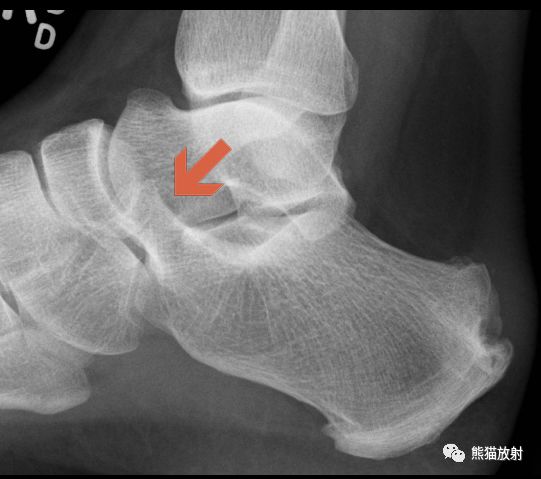

先看一个病例:患者,男性,16岁,足部疼痛。

足正侧位平片

食蚁兽鼻征

1、足侧位X线片上。

2、食蚁兽的鼻子:跟骨的前上部管状伸长,接近舟骨或与其重叠。

3、提示跟舟联合

跟舟联合在侧位X线片上呈现食蚁兽鼻征,拍摄45°内斜位X片观察跟舟联合